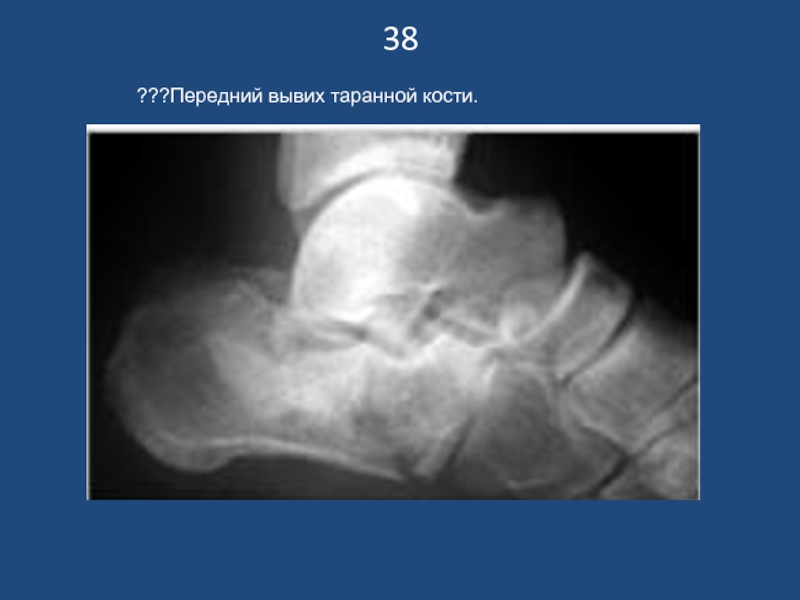

Слайд 3938

???Передний вывих таранной кости.